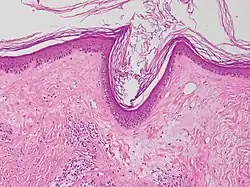

Diagnosis is generally by examination.[2] It can be confirmed by skin biopsy, which shows thick dermal collagen and thin epidermis.[2] LS may appear similar to guttate morphea, lichen planus, and lichen simplex chronicus.[1] Treatment involves strong topical steroids.[2] Sometimes, particularly in children, it gets better without further treatment.[2]

A biopsy of the affected skin can be done to confirm diagnosis. When a biopsy is done, hyperkeratosis, atrophic epidermis, sclerosis of dermis and lymphocyte activity in dermis are histological findings associated with LS.[23] The biopsies are also checked for signs of dysplasia.[24]